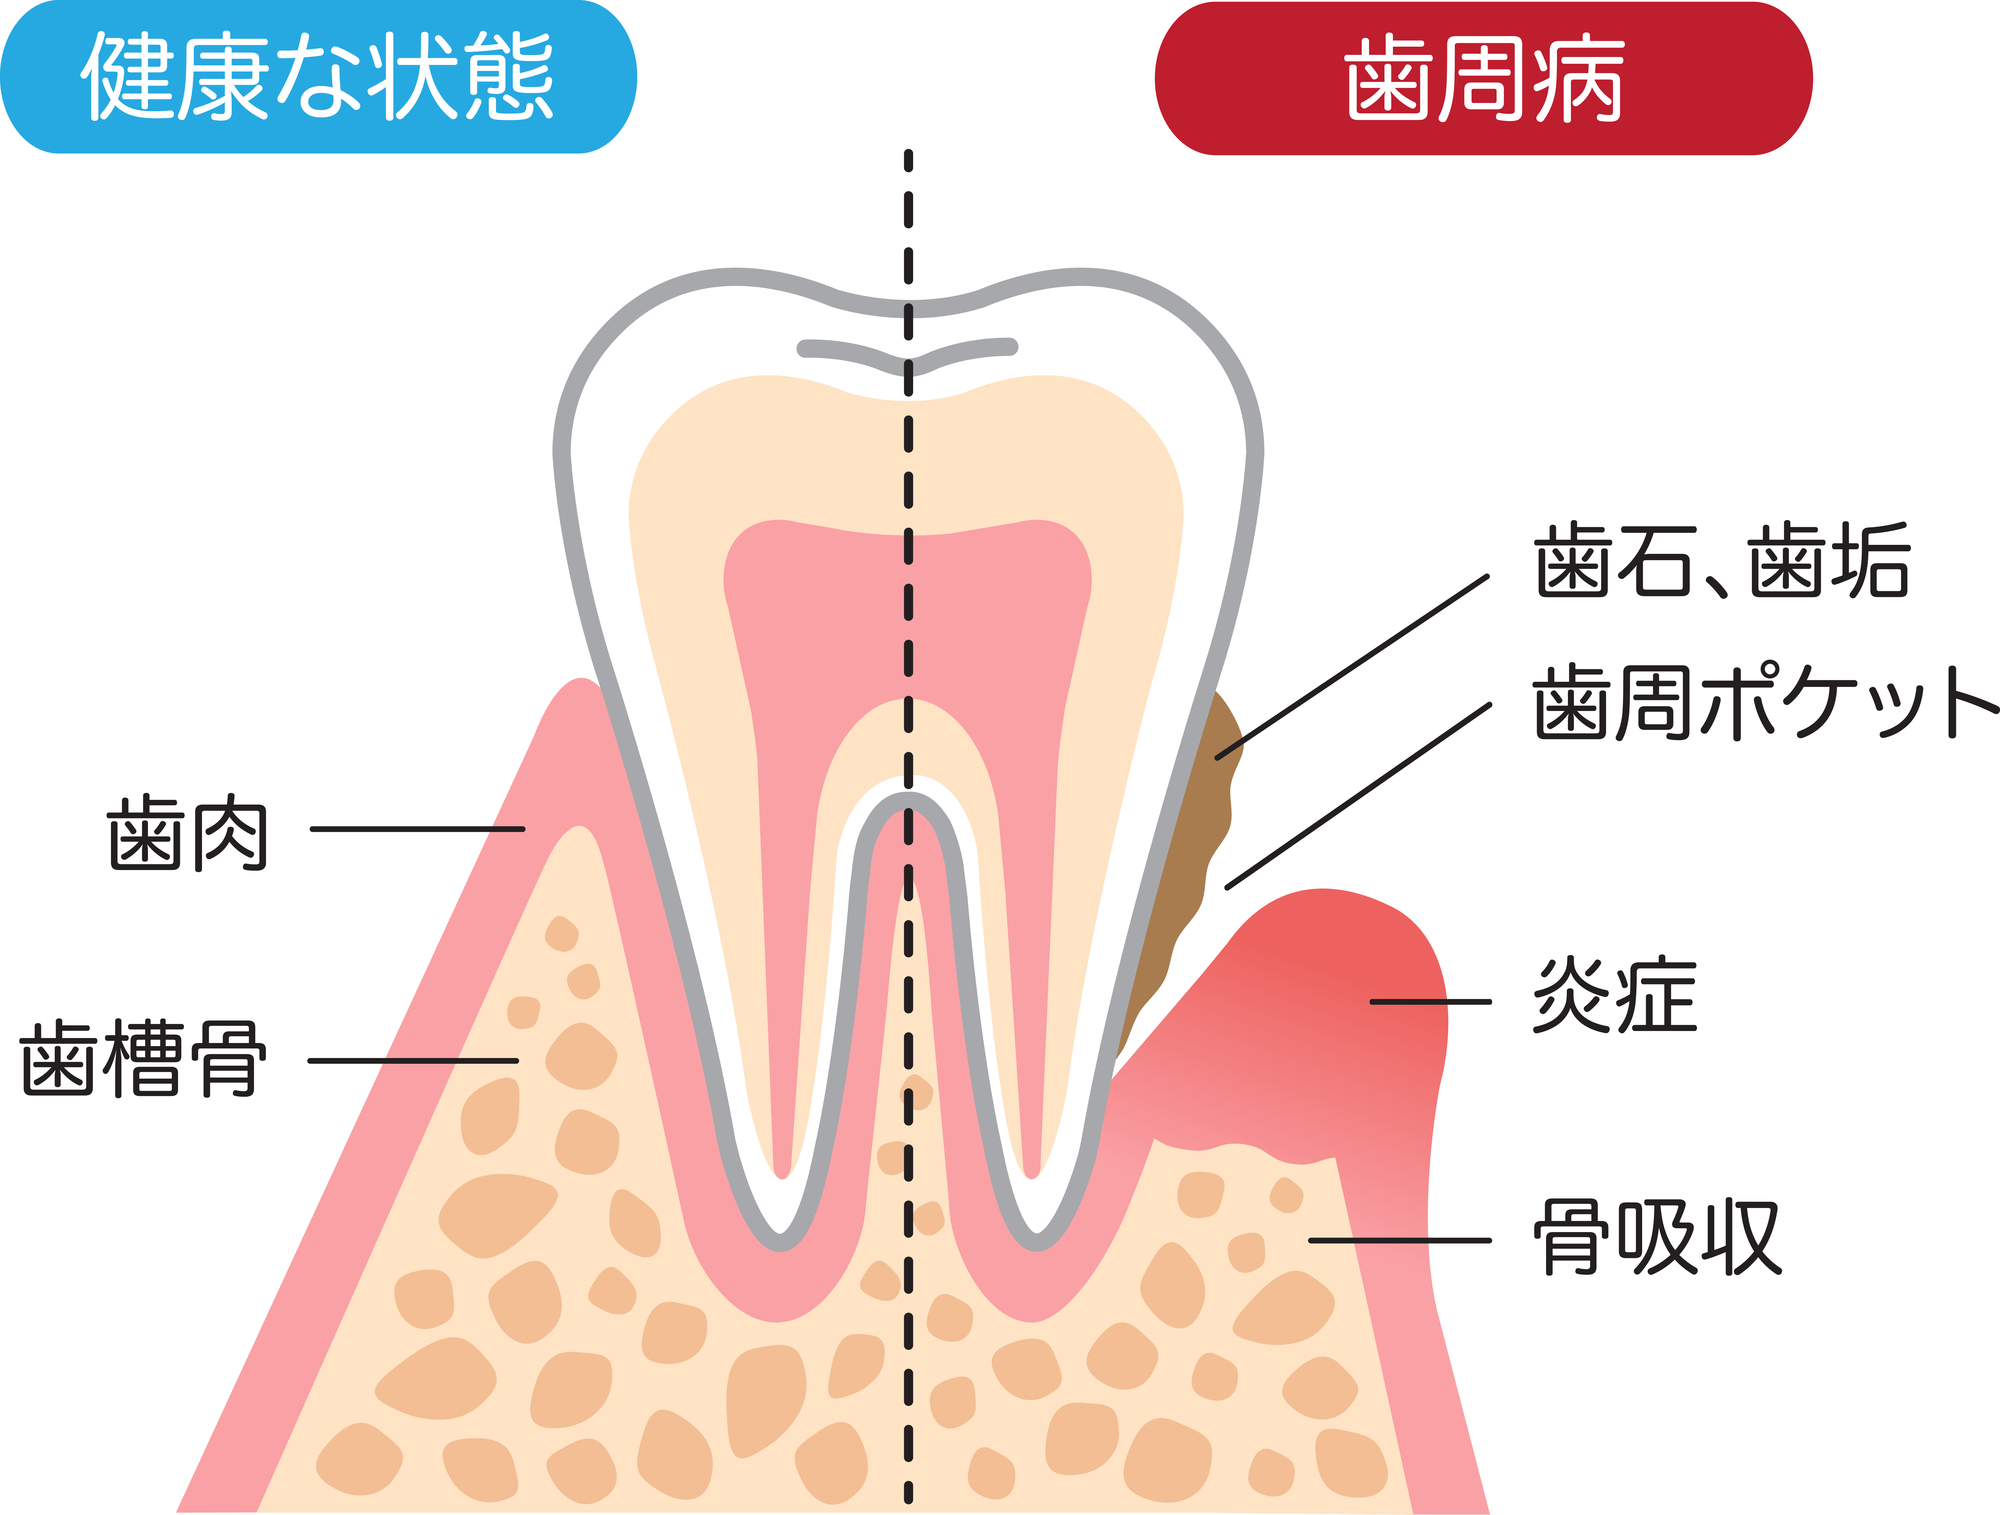

歯周病でも矯正治療できる?歯並びと歯周病の関係